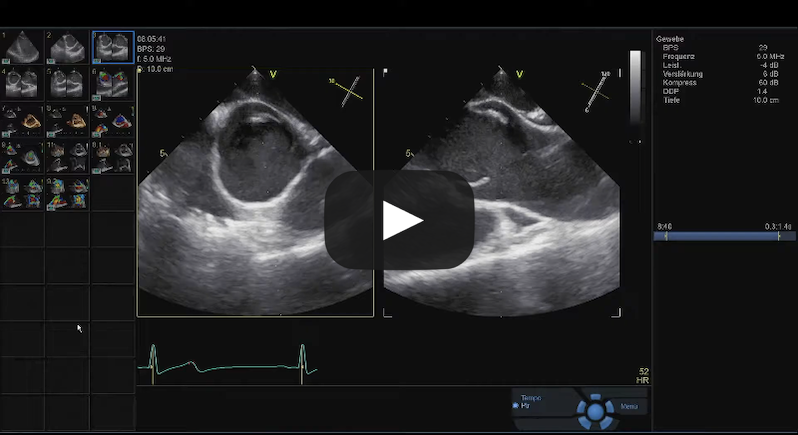

Tricuspid Aortic Valve Repair

Source: Cardiac Research & Education Saar GmbH, used with permission.